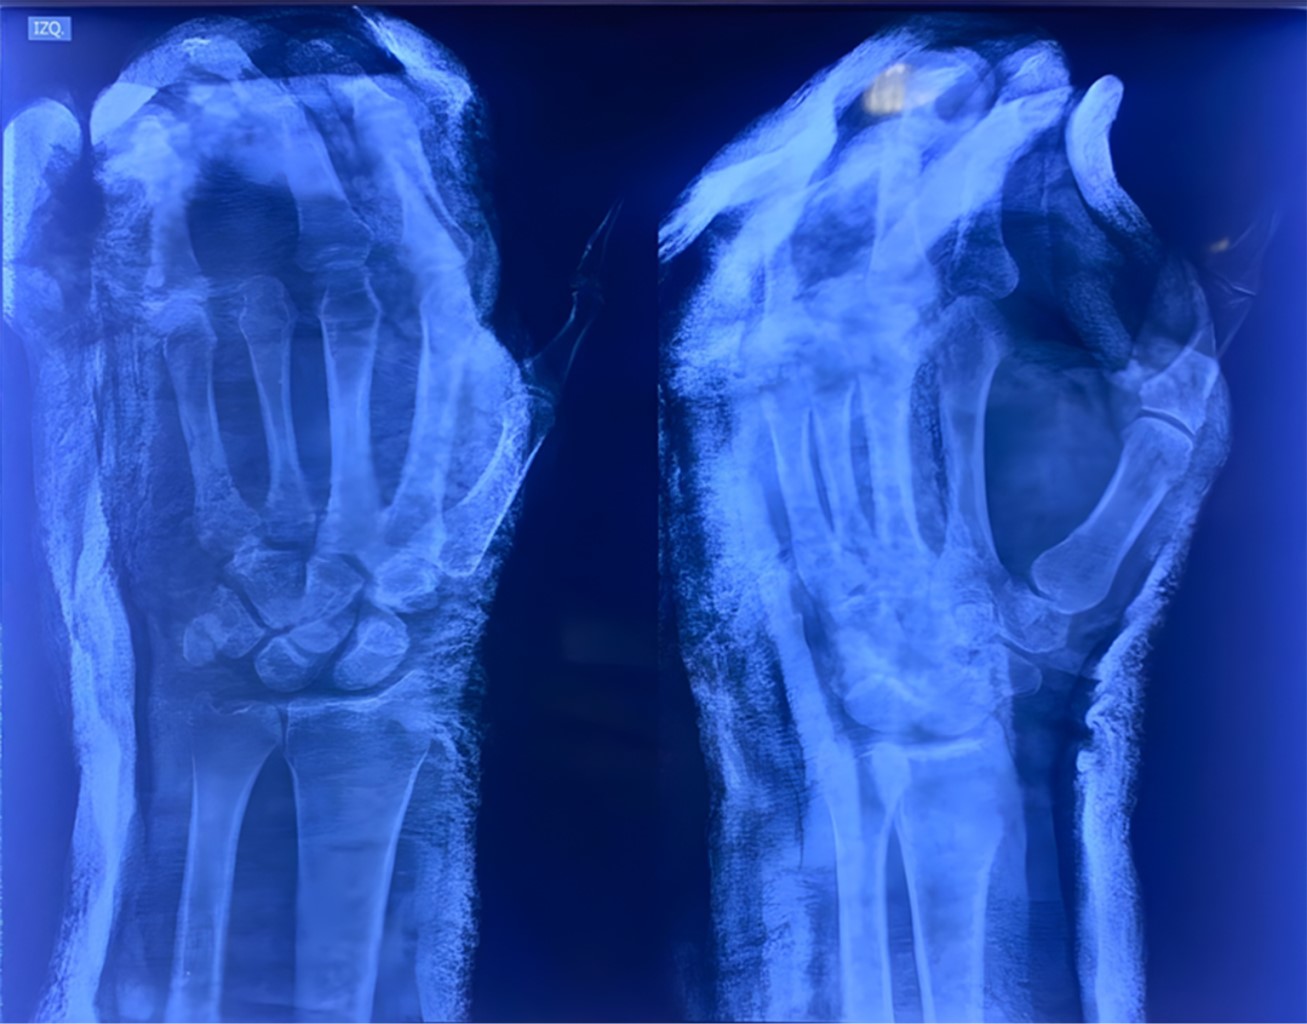

Paciente masculino de 48 años de edad, quien ingresa a nuestra unidad hospitalaria tras presentar lesión en mano izquierda posterior a carga axial, así como compresión al ser arrollado por vehículo automotor; a su ingreso, se identifica incongruencia articular en las líneas de Gilula (Figuras 1 y 2).

Además de presentar fractura en metáfisis proximal con extensión a metáfisis distal de F2 de tercer dedo, amputación traumática con desarticulación de F1-F2 más denudamiento de cuarto dedo, herida cruenta de quinto dedo más lesión del extensor propio del quinto dedo en zona V. A su ingreso pasa a cirugía de control de daños más reducción cerrada de luxación peri-escafo-transtrapecio-transtrapezoidea (Figura 3).